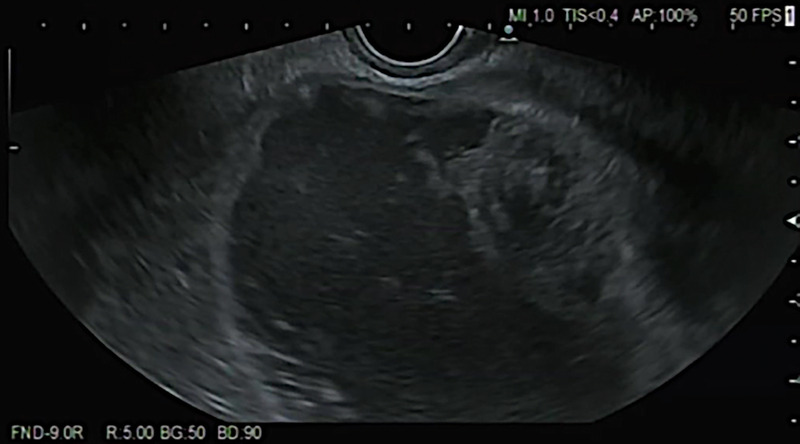

EUS-guided aspirate of a traumatic paraduodenal duodenal hematoma with gastric outlet obstruction (with videos).

eus引导下的外伤性十二指肠旁血肿伴胃出口梗阻的抽吸术(附录像)。